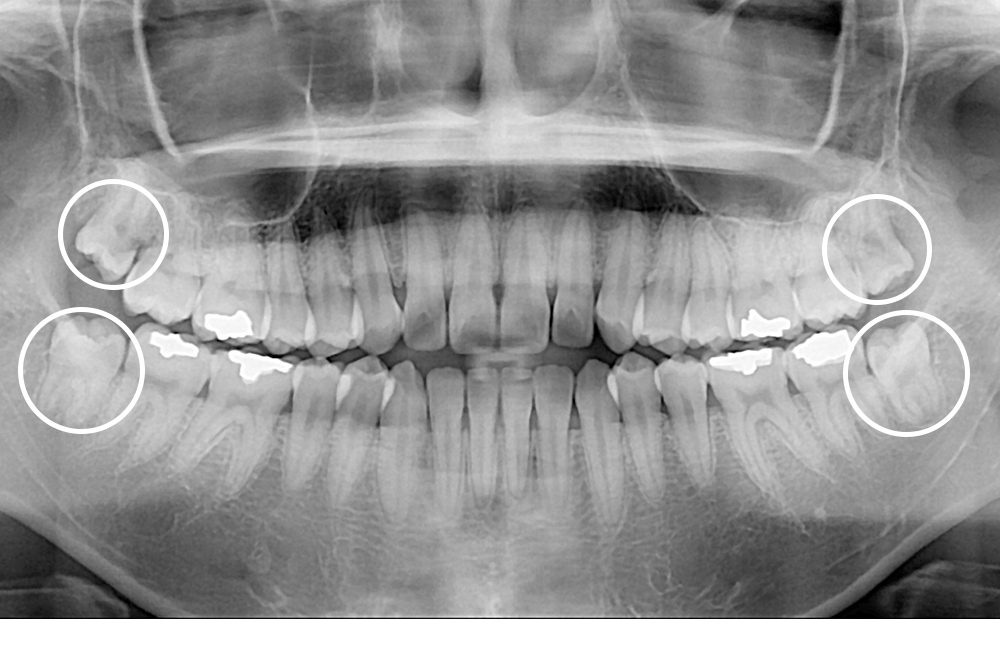

[사랑니] 매복 사랑니 발치

치료전 : 2021-02-04